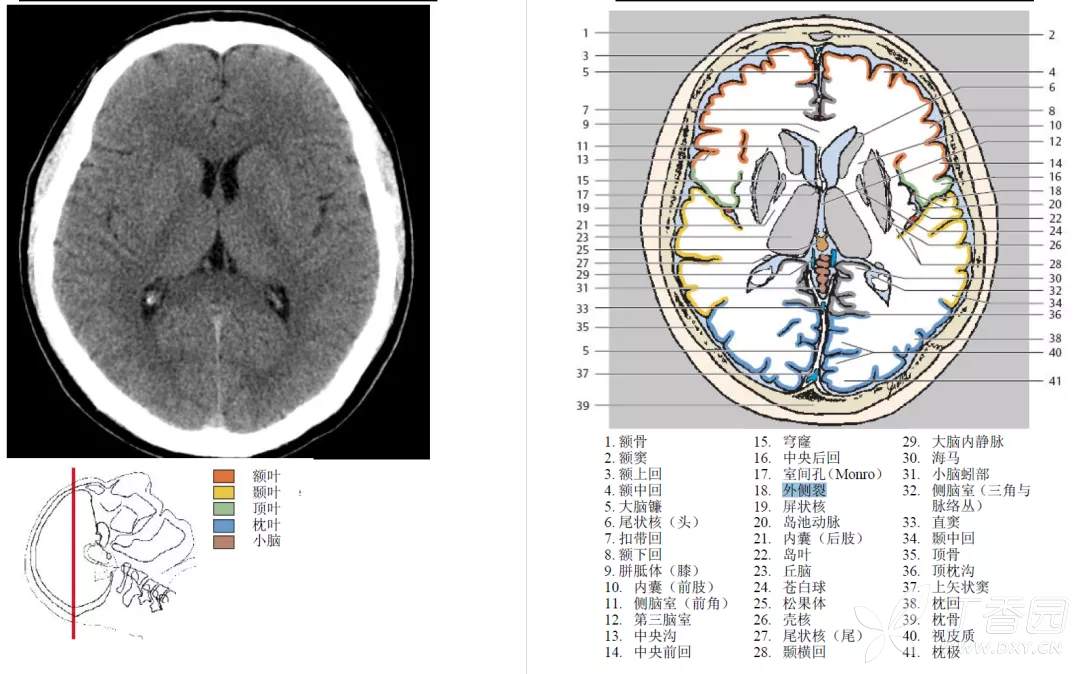

由于脑池和脑室内均为低密度的脑脊液,有时影像上二者易于混淆。因此,熟悉脑池的断层影像解剖,对病变的影像学定位诊断至关重要。MRI 可较好地显示脑池及内含结构。CT 平扫即可观察较低密度的脑池。

大脑外侧窝池

大脑外侧窝池 cistern of lateral fossa of cerebrum 又名侧裂池,位于大脑外侧窝内。

大脑外侧窝池在横断面上的典型表现呈横置的 “Y” 形,主干伸至岛叶表面即分为前后两支,前支较短伸向前内,后支较长伸向后方。

其中前后支又称为岛池,内侧对应的脑皮质即为脑岛叶。

大脑外侧窝池内有大脑中动脉的岛叶段和大脑中静脉经过大脑外侧窝池在青年人可以不明显,老年人常较清晰,脑萎缩者明显增宽。